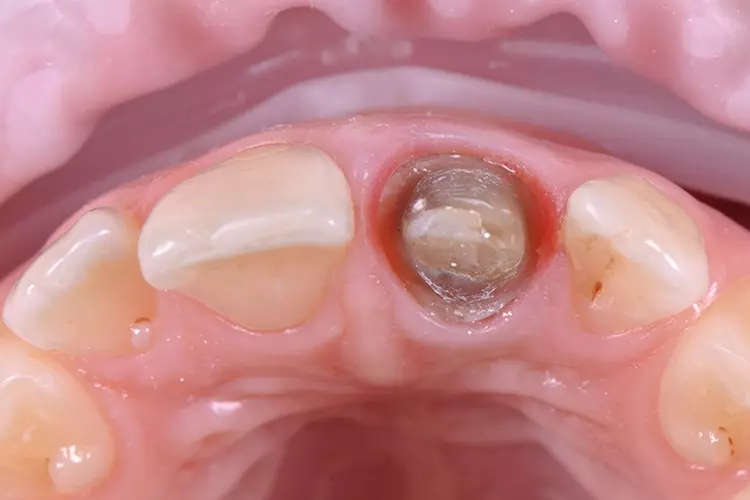

Auf den vorab hergestellten Situationsmodellen wurde für die provisorische Versorgung eine Tiefziehfolie für den Oberkiefer hergestellt. Es erfolgte die schonende Abnahme der Einzelzahnrestauration und die Entfernung des Befestigungsmaterials.

Die vorgefundene Präparation konnte im labialen Bereich in 3 Ebenen anatomisch reduziert und optimiert werden. Bei der Platzierung des zirkulären Präparationsrandes war die „biologische Breite“ nicht berücksichtigt worden und der Kronenrand lag deutlich subgingival.

Die Gingiva wurde mithilfe eines Retraktionsfadens vorsichtig verdrängt und die zirkuläre Präparation mit einer ausgeprägten Hohlkehle klar definiert. Beim Langzeitprovisorium, welches man in der Praxis herstellte, wurden sämtliche ästhetischen und funktionellen Parameter berücksichtigt und die „äußere Hülle“ der definitiven Krone festgelegt.